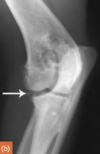

Kissing lesion - Sclerosis of the medial humeral condyle (arrowed); this accompanies MCP fragmentation

4-year-old Rottweiler

large separate medial coronoid fragment superimposed on the cranial radius (arrowed). Osteophytic reactions are seen on the cranial margins of the joint and on the anconeal process and subtrochlear sclerosis.